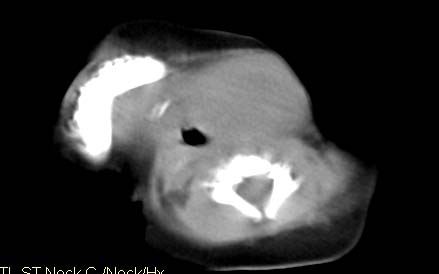

男,26天,发现左侧颈部包块5天,质较硬,患儿不哭不吵,无明显发热,头向右侧歪斜,其父母诉患儿出生时正常,昨天查血象wbc19.4×10的9次方/l,b超考虑来源于甲状腺的恶性肿瘤,我科认为肿块内有低密度区,而且病程发展较快,血象高,考虑炎性病变可能大。患儿年龄太小没做增强。请大家提出高见。

男,26天,发现左侧颈部包块5天,质较硬,患儿不哭不吵,无明显发热,头向右侧歪斜,其父母诉患儿出生时正常,昨天查血象wbc19.4×10的9次方/l,b超考虑来源于甲状腺的恶性肿瘤,我科认为肿块内有低密度区,而且病程发展较快,应该首先排除血肿,其次考虑感染

随访结果:炎症(患儿经过一星期抗炎治疗后颈部包块明显缩小,现已经正常)。